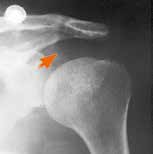

Die Ergebnisse des Literaturreviews konnten somit nur eine klinische Studie identifizieren, die die Wirkung einer Schulter-Funktionsorthese im Zusammenhang mit einem SHS untersuchte. Die Neuro-Lux®-Orthese ist laut Herstellerangaben bei Schultersubluxation und zur Reduktion eines SHS indiziert 3637. Hartwig et al. konnten eine signifikante klinische Wirksamkeit der Schultergelenk-Funktionsorthese Neuro-Lux® zur Vermeidung bzw. zur Minderung eines bestehenden SHS nachweisen. Damit ist Neuro-Lux® derzeit die einzige Orthese, die eine Schultersubluxation effektiv vermindert (Abb. 4 38) und dabei eine freie Beweglichkeit des Arms und somit eine effektive Therapie zulässt.